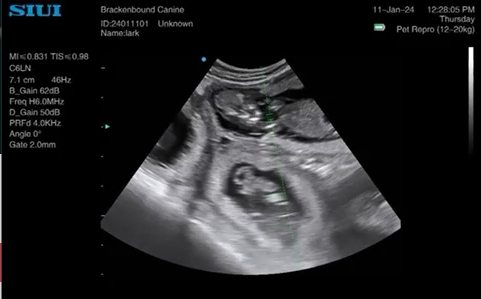

This feline scan was performed at 52 days following a 30 day scan suggesting a singleton kitten. The linear probe was used. The mother delivered the kitten without issue.